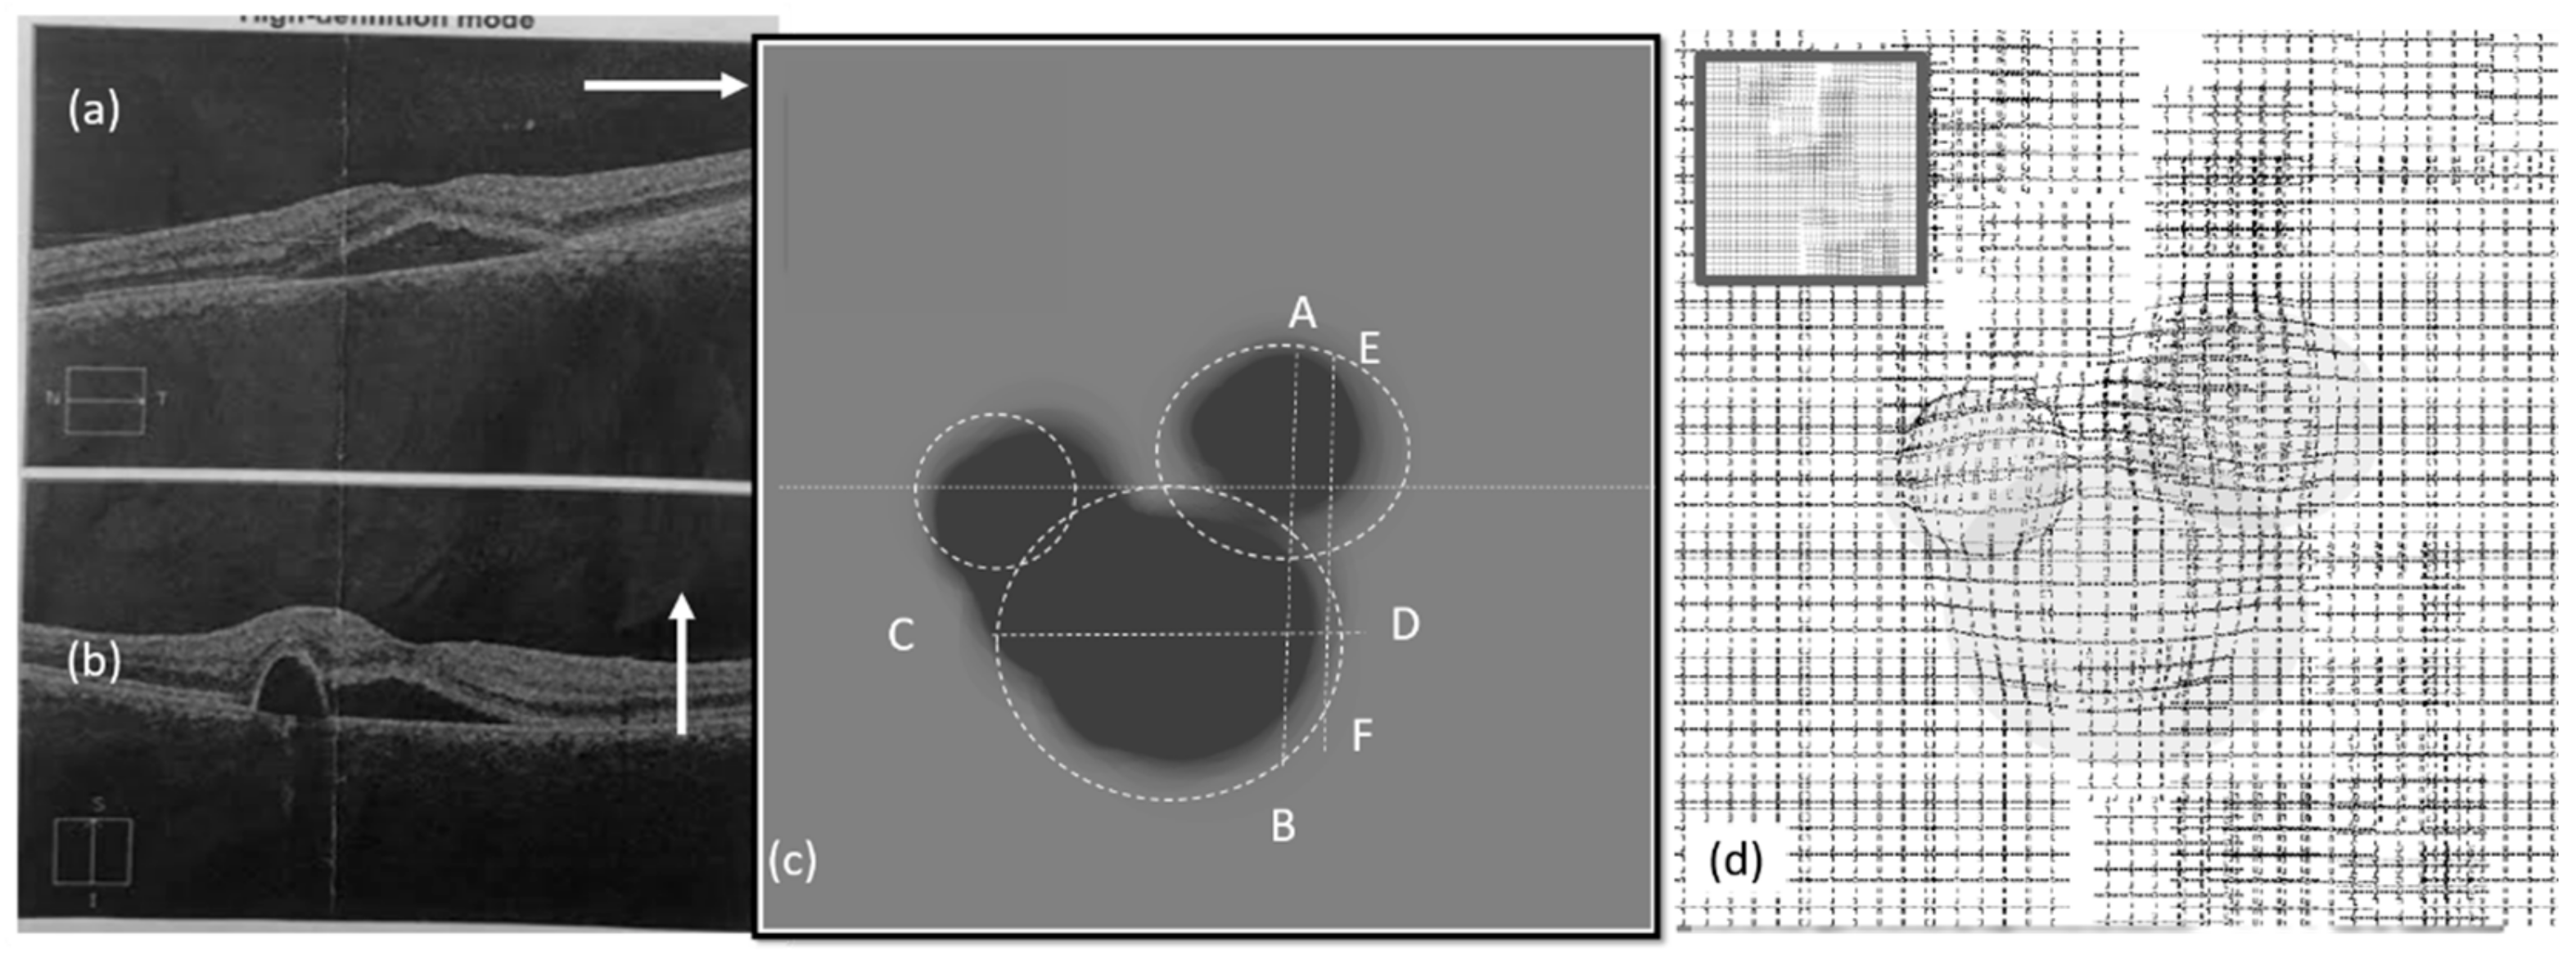

3.1. Effect of CSR in the Visual Field

3.2. Spherical Shape CSR Modeling

5.1. Simulation Results of CSR Modeling